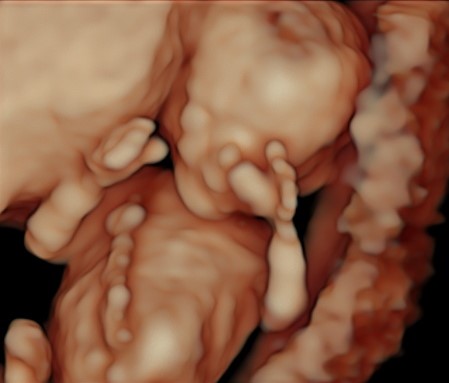

In questi 4/5 centimetri la risoluzione degli apparecchi moderni riesce a fare una prima valutazione morfologica, per vedere che ci siano tutti i “necessori” ed eventualmente anche accessori: cercando è possibile evidenziare il tubercolo genitale (sempre che il piccolo decida di essere collaborante e mostrare le proprie grazie). Si chiama così perché clitoride e pisellino hanno le stesse dimensioni a questa epoca, ma è possibile riconoscerli in base all’angolo rispetto al corpo: parallelo al corpo per le signorine, verso l’alto per i maschietti. Attenzione però la sensibilità, ovvero quanto ci azzecchiamo, è intorno al 60%.

La parte morfologica è molto importante, riusciamo a studiare l’estremo cefalico – a questa epoca il cervello fetale è molto semplice – , il massiccio facciale con occhi, naso bocca, le orecchie sono abbastanza facili da essere evidenziate. Nel torace oltre ai campi polmonari possiamo vedere il cuore battere ritmicamente e confermare la presenza delle quattro camere cardiache. Nell’addome riusciamo ad evidenziare lo stomaco e l’inserzione del cordone ombelicale. Si nota la presenza della vescica e del tubercolo genitale. Si possono esplorare tutti e quattro gli arti.

Per i genitori vedere sotto i propri occhi prendere forma il tesorino risulta una esperienza indimenticabile e impareggiabile al limite fra incredulità e la sorpresa come tutto sia già presente seppur in scala ridotta.